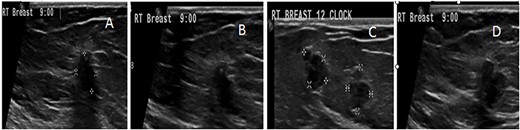

US follow-up after the first biopsy revealed several findings: (A) the most outer lesion can be seen at 9:00 and became vertically oriented inside the breast parenchyma with irregular serrated margins; it infiltrated the adjacent breast parenchyma and the deep posterior acoustic shadow. (B) A tiny microcalcification can be seen at its upper pole. (C and D) An enlargement of the previously seen mass lesions after a second biopsy in which all of them have microlobulated borders and are longitudinally oriented inside the breast tissue can be observed.

Five months later, she returned for medical treatment, and US follow-up revealed some changes in the two most suspicious lesions; one of them had become longitudinally oriented with posterior acoustic shadowing, irregular infiltrating serrated borders, and tiny microcalcifications inside. The other lesion was mildly enlarged with microlobulated outer borders (Fig. 4). Typical malignant US features were found; so the outer lesion was upgraded to a BI-RADS V classification (Fig. 4). A decision was made to repeat the biopsy, which showed ADH with no infiltrating malignancy (Fig. 5). The patient was counseled regarding her diagnoses and the proposed management plan, which was open excision of the two highly suspicious lesions, yet she insisted on having a right simple mastectomy. The risks and possible postoperative complications of the chosen type of operation were explained to her and her family, and they agreed to proceed. Due to the high malignant potential of right breast lesions and the patient’s desire for simple mastectomy, a right simple mastectomy with sentinel lymph nodes biopsy was performed.